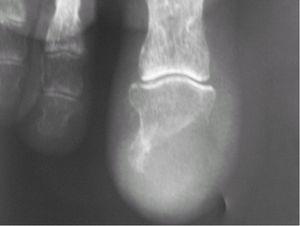

Fig. 2.--Radiografía del dedo afectado en la que se observa osteolisis de la falange distal sin reacción perióstica asociada.